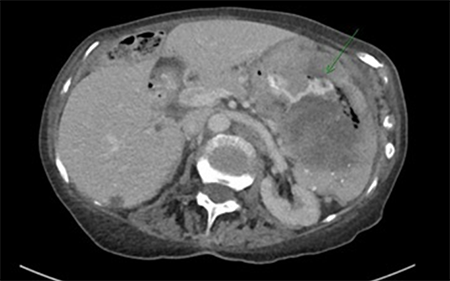

A spiral computerized tomography (CT) scan of the chest was initially performed to rule out pulmonary embolism. Although none was seen, an incidental large left pleural effusion was visualized. Additionally, there was concern for fistulization into the greater curvature of the stomach from the previously followed splenic mass (Figure 1).

Figure 1. Axial imaging demonstrating oral contrast passing between the stomach and the splenic mass through a fistulous tract

The anterior surface of the mass appeared to invade the greater curvature of the stomach, with ingested oral contrast extending through a fistulous tract between the two. Additionally, the mass directly abutted the left hemidiaphragm, the transverse colon, and the tail of the pancreas.